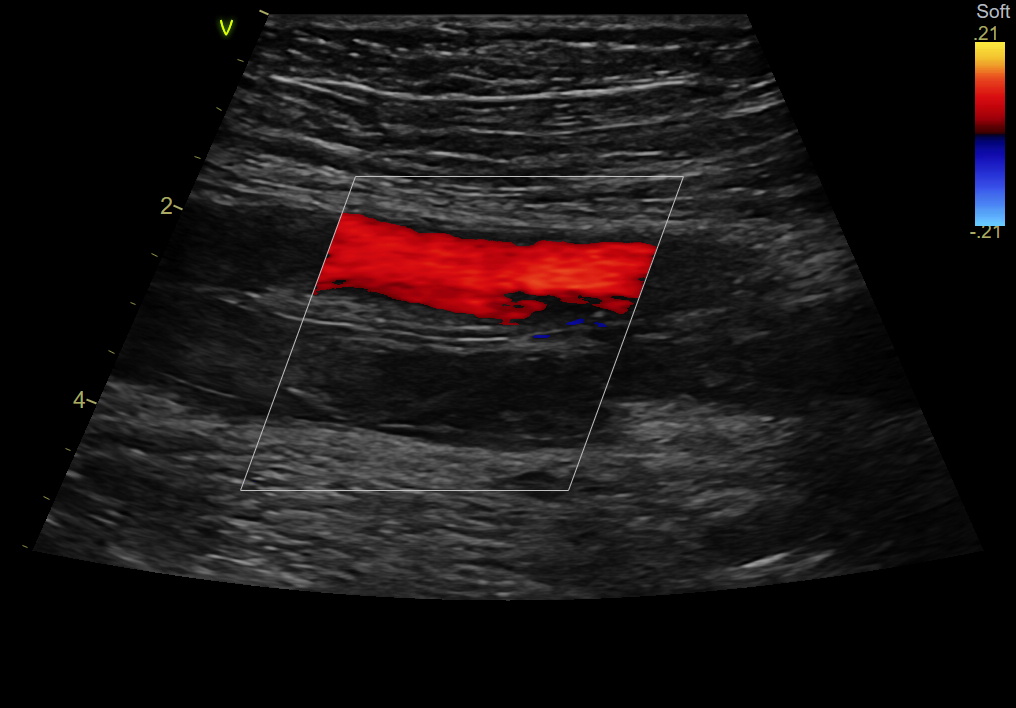

Тромбоз вен нижних конечностей (ТВНК) — опасное состояние, при котором в глубоких или поверхностных венах образуются кровяные сгустки. Без своевременной диагностики и лечения он может привести к жизнеугрожающим осложнениям, включая тромбоэмболию легочной артерии (ТЭЛА).

В нашем отделении, в частности доктором Казаковой А.И. ежемесячно выявляются десятки подобных случаев.

БУЗ ВО ВОНКОЦ Отделение ультразвуковой диагностики